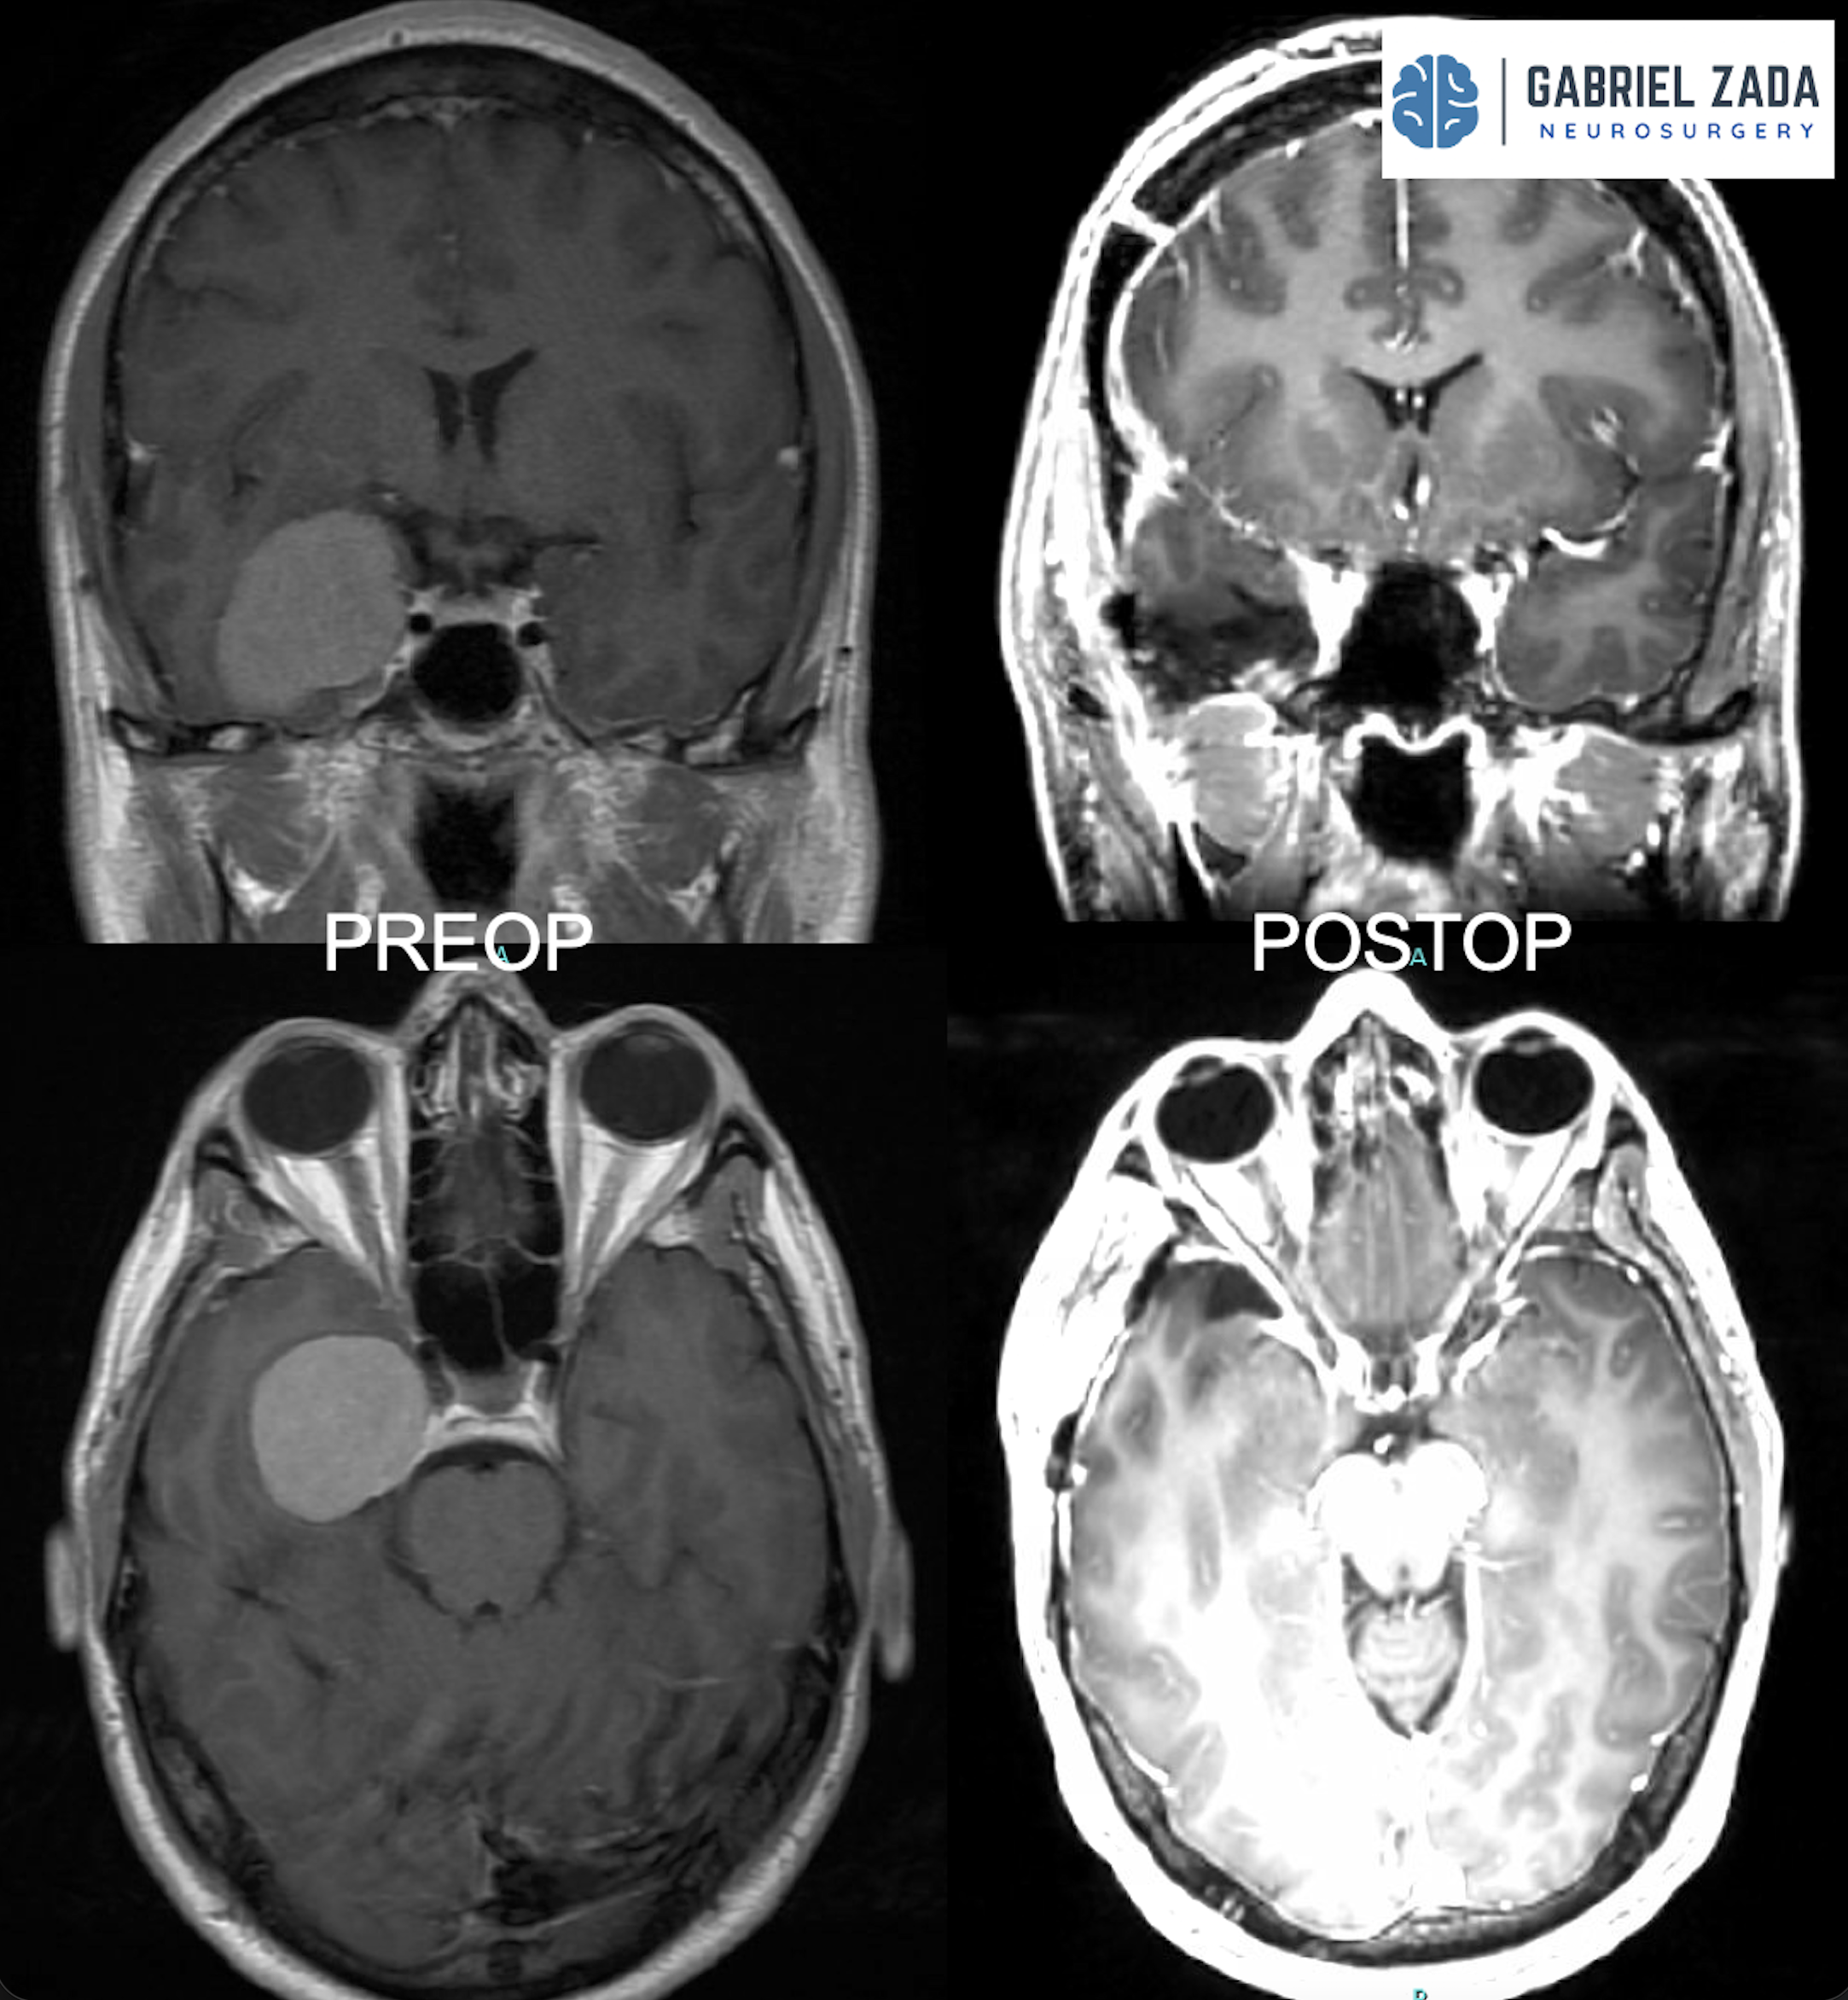

Explore this comprehensive gallery featuring pre‑ and post‑operative imaging of patients with skull‑base tumors treated by Gabriel Zada, MD, MS, FAANS, FACS. These cases highlight Dr. Zada’s expertise in advanced neurosurgical techniques and outcomes.

*Representative cases shown for educational purposes. All images de-identified. Individual results vary.